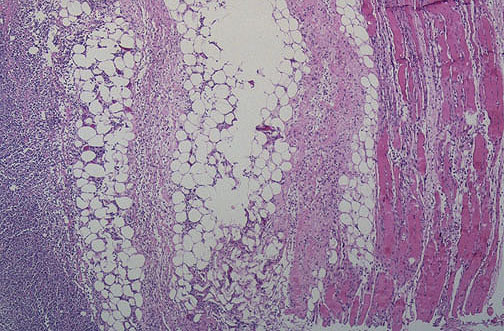

At low magnification, extensive inflammation can be seen throughout the muscle and adjacent fibroconnective tissue and adipose tissue of the thigh. This is necrotizing fasciitis.